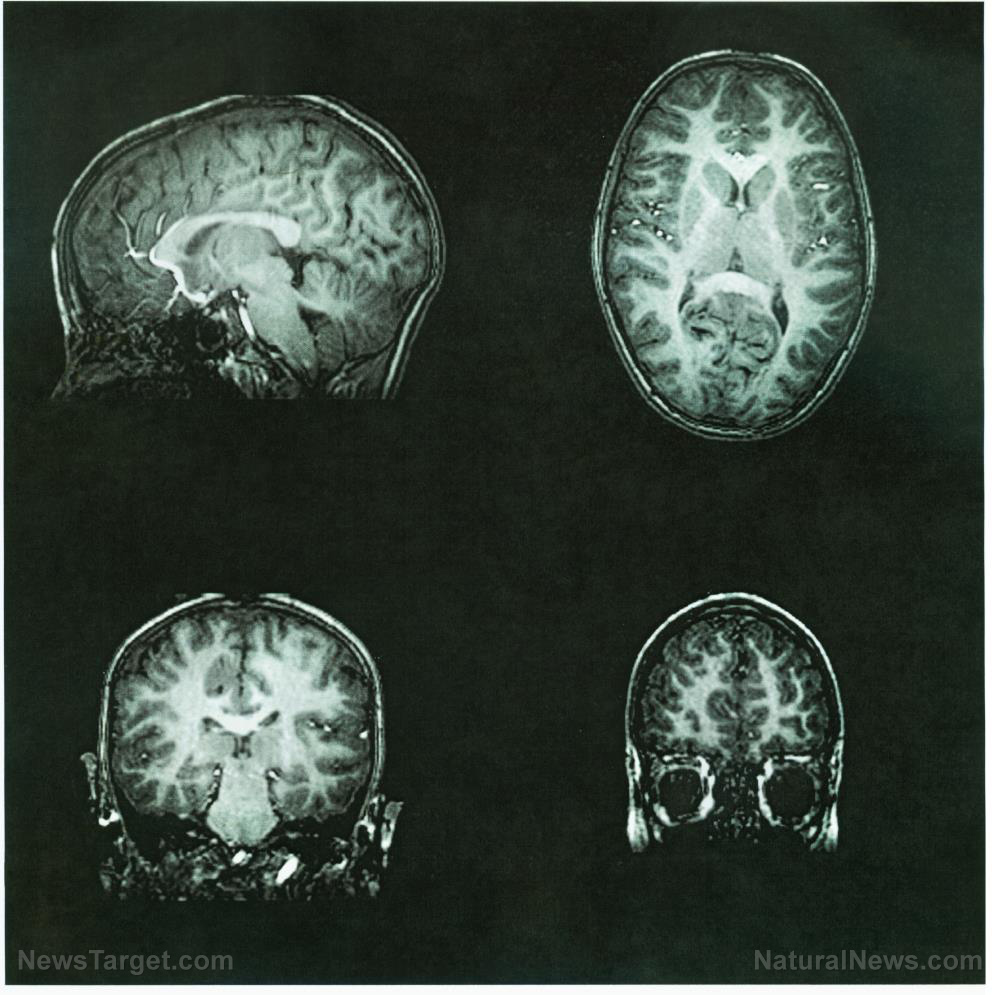

Neurological damage linked to Alzheimer’s may be repaired with dietary supplementation

Is it really possible to mitigate and even reverse the damaging effects of Alzheimer’s disease and dementia through simple dietary supplementation? According to new research out of Denmark, it certainly is. Professor Vilhelm Bohr and an international team of scientists hailing from the Center for Healthy Aging at the University of Copenhagen and the American […]